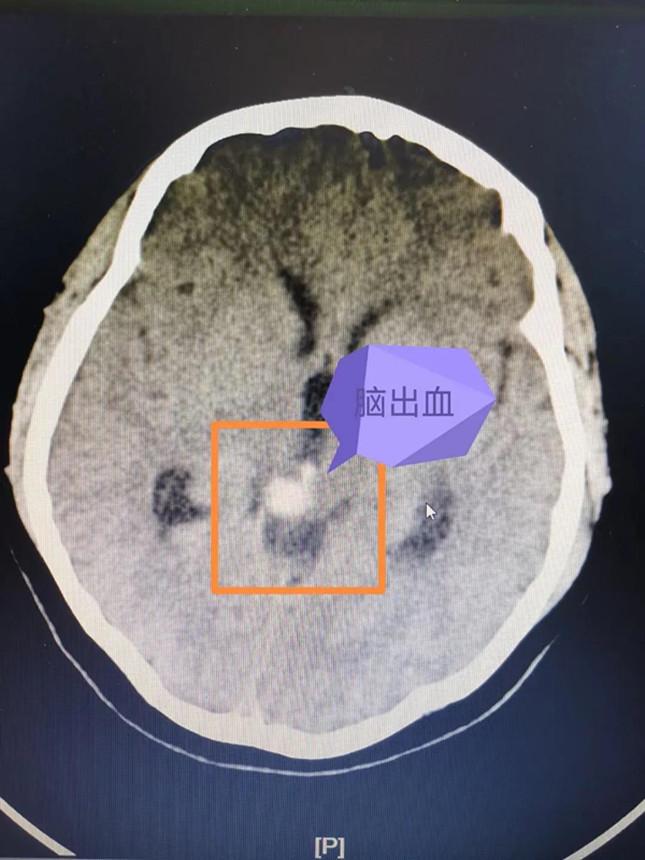

经过头颅CT检查,接诊的巴特尔副主任医师发现大梅存在着非常危险的脑干出血,对于没有高血压病史的年轻患者,他立即想到了脑血管疾病的可能性,于是很快进行了头颅MR检查,发现脑干出血周边有可疑的异常脑血管影,初步确定了之前的推测。

脑血管畸形是一种先天性的脑血管疾病,脑出血是脑血管疾病最常见的发病表现。已经有过出血的脑血管畸形随时有再次破裂的风险。而核桃大小的脑干是生命中枢,掌管着人体的呼吸、心跳、体温等最基础的功能。脑干出血属于脑出血中最危险的一种,通常情况下,哪怕是2~3毫升的脑干出血都可能引起严重后果,一旦出血量超过5毫升,死亡率高达70%以上。大梅的生命危在旦夕,却又无法长途转运。而且脑干周围的脑血管畸形的治疗极其复杂,风险极高,如何成功“拆弹”、挽救患者的性命,巴特尔医生心里没底。